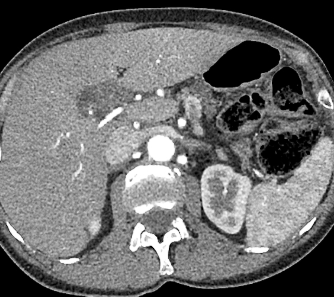

Na TC a avaliação é feita na fase pré-contraste. Avalia-se objetivamente através do valor absoluto e comparativo do ROI (diferença >5 entre fígado e baço) e subjetivamente através da visualização dos vasos.

Verdadeiro.

A lesão hipoatenuante próxima ao hilo hepático corresponde a um nódulo a ser esclarecido.

Falso.

A lesão hipoatenuante próxima ao hilo hepático corresponde a área poupada de esteatose.